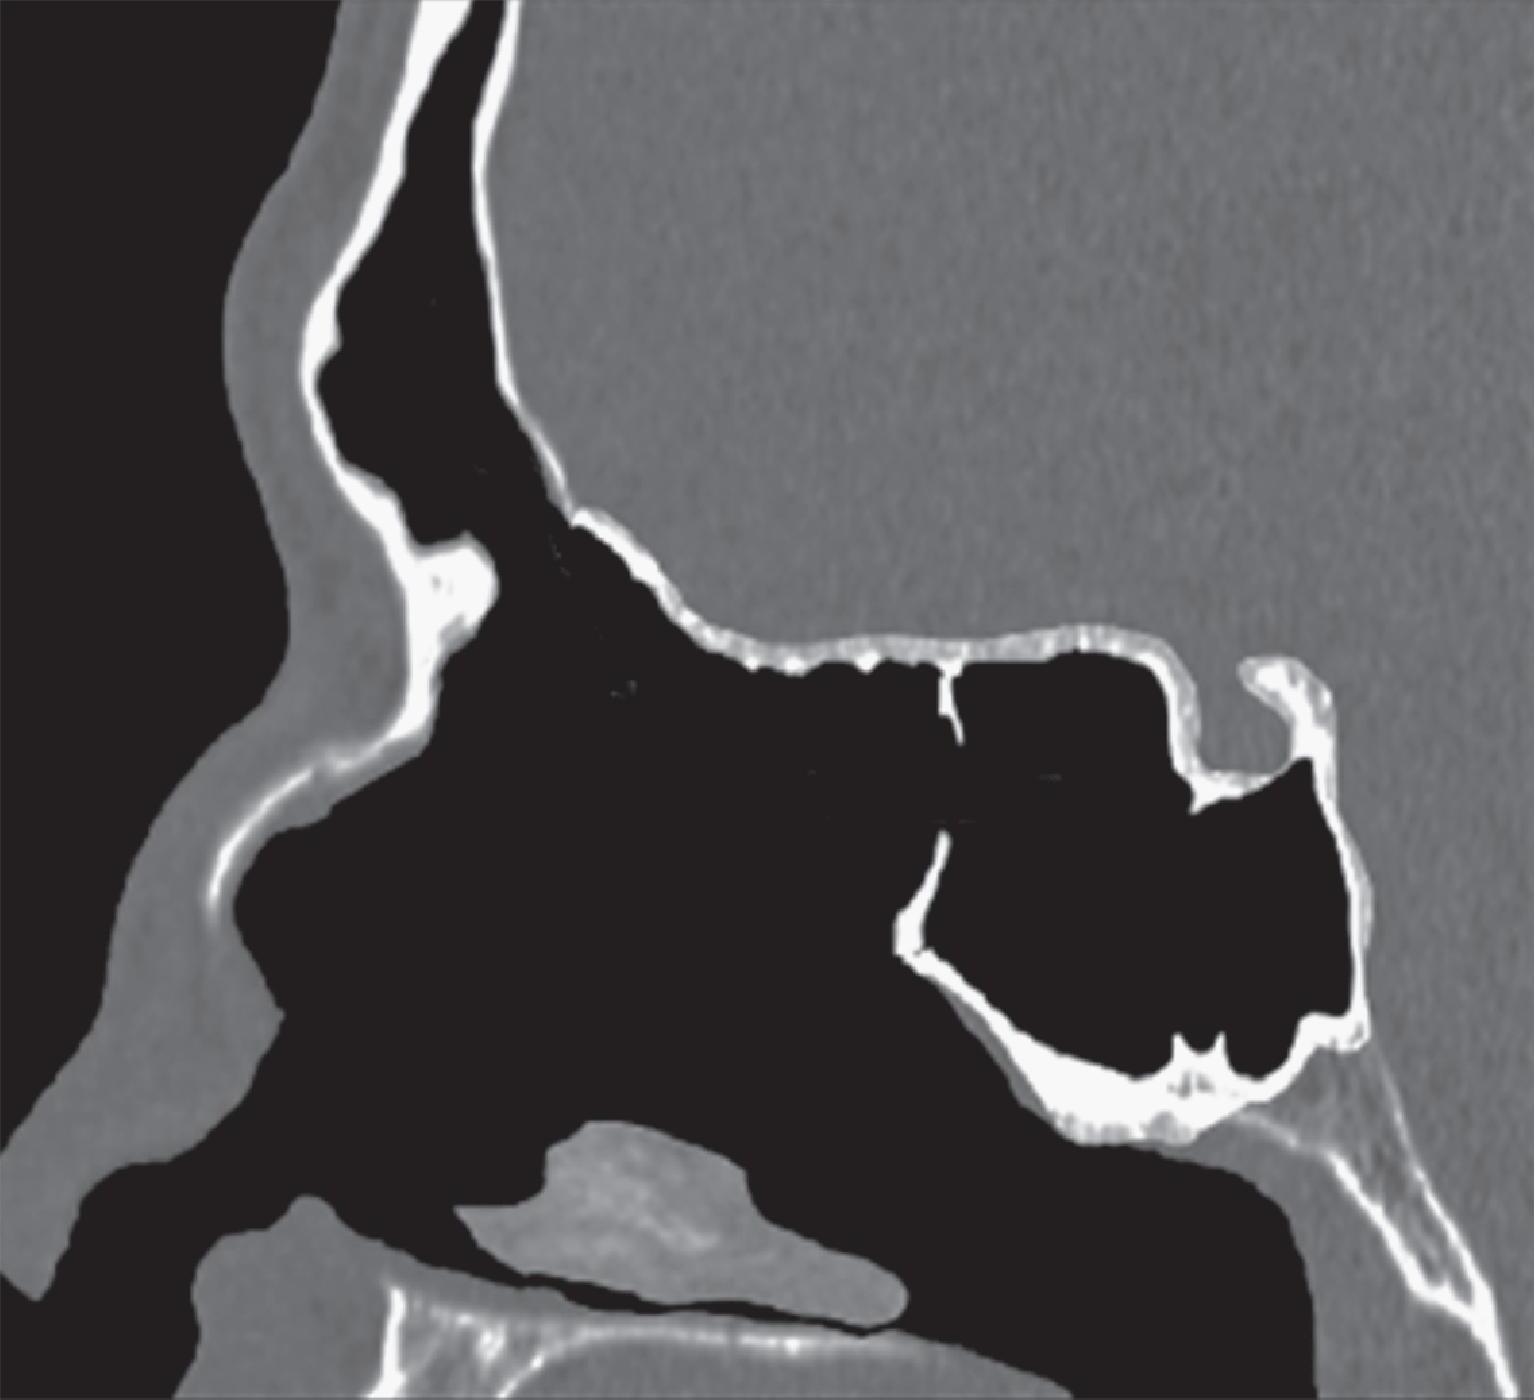

1-4. TC e reconstrução 3D com destaque para estrutura etmoidal (em vermelho), funcionando como câmaras de baixa pressão para drenagem do seio maxilar.

1-7. TC com reconstrução 3D mostrando em vermelho apenas o seio etmoidal e não o osso etmoidal, e sua relação com a fossa nasal, o seio maxilar, órbita e fossa anterior.

Este complexo anatômico chamado seio etmoidal, controla a pressão e o fluxo aéreo que penetra nos verdadeiros seios paranasais e pode ser interpretado como um sistema de câmaras aerodinâmicas de baixa pressão cuja topografia particular faz dele o centro anatomofuncional do aparelho rinossinusal.

Na estrutura do seio etmoidal as câmaras aerodinâmicas denominadas meatos, oferecem um espaço fisiológico definido para os seios esfenoidal, maxilar e frontal e são dispostas arquitetonicamente para impedir que o fluxo inspiratório (rápido, frio e seco) penetre nestas cavidades, e permitir a entrada do fluxo expiratório (lento, aquecido e úmido). Existem pelo menos duas e as vezes três câmaras etmoidais na parede lateral do nariz que são os meatos, médio, superior e supremo.